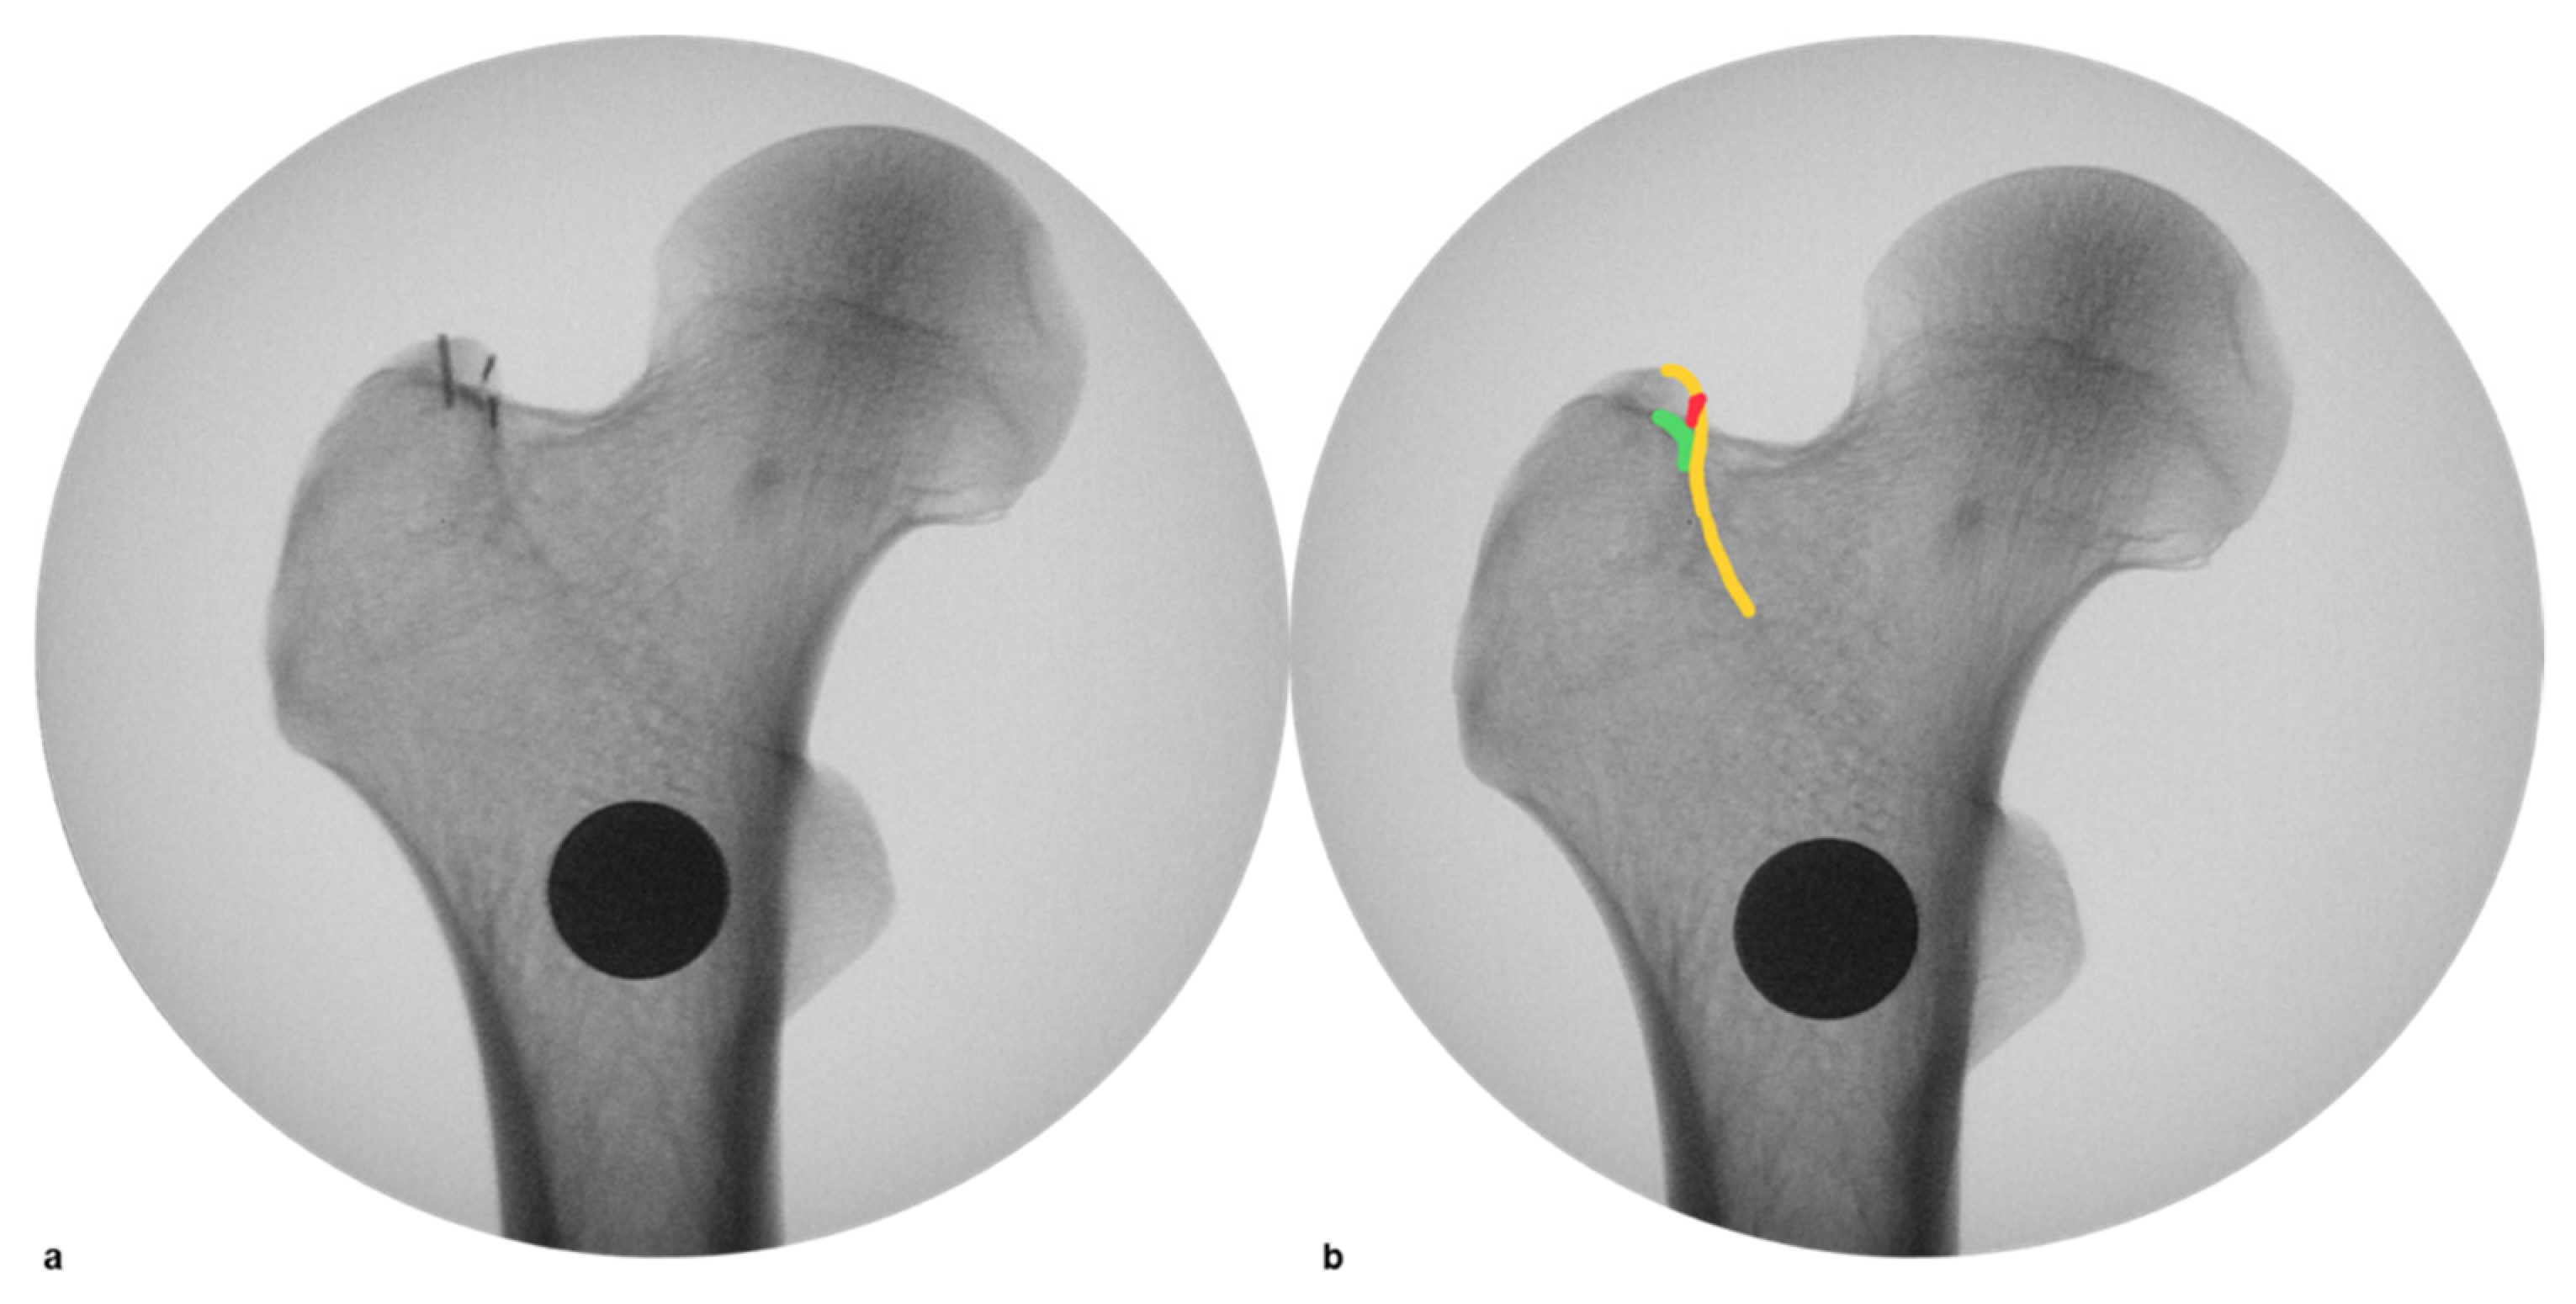

3.4. Plate Position as a Risk Factor for Plate Removal